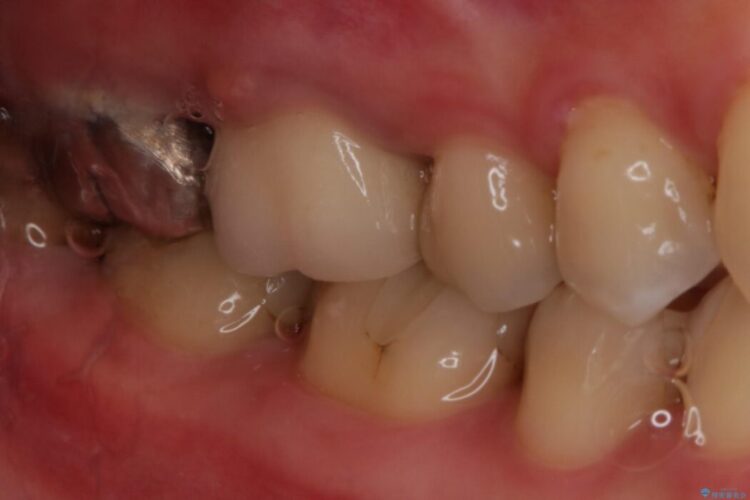

別の部位の治療で通われていた患者様ですが、歯ぐきにできものが繰り返しできるとのことで相談されました。

根管治療を再度行うことでフィステル(ニキビのようなできもの)は消失しました。